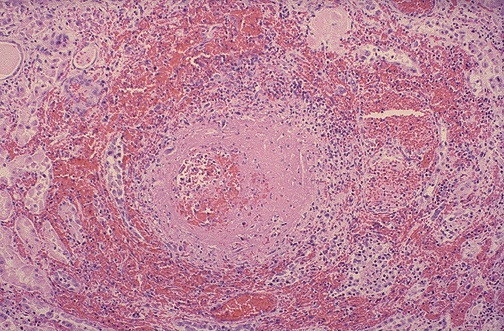

Image 3.4

There is fibrinoid necrosis of the small artery with surrounding hemorrhage.